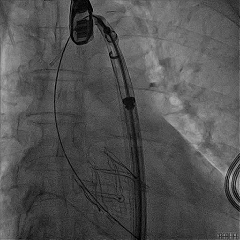

TEER手术过程

建立右侧股静脉入路,在食道超声引导下进行房间隔穿刺,获得穿刺高度4.1cm,交换Super Stiff超硬导丝至左上肺静脉,使用血管鞘扩张股静脉后,沿超硬导丝送入可操控导引导管(SGC)至左房,将第一枚二尖瓣夹输送系统(CDS-XTR)送入左心房。送入夹子过程中为避免碰到左房组织完成Straddle“骑跨”,顺利完成Straddle并将夹子打弯至二尖瓣环水平。接下来为避免发生缠绕在1区进行轨迹测试,使夹子的运动轨迹指向心尖。在心房侧打开夹臂,调整夹臂方向指向12点-6点方位,与二尖瓣对合缘垂直。完成调整后将夹子移动至3区位置,将二尖瓣夹关紧后缓慢送入左心室。在左室打开夹子重新确认Orientation。准确成功捕捞3区前叶脱垂及反流区域,确认瓣叶瓣尖稳定插入夹臂后,Gripper Down,观察到明显Bouncing后,关紧夹臂予以夹合,夹子内侧反流消失,夹子外侧还有残余脱垂及中量反流。考虑瓣叶长度11mm以上,瓣口面积足够,决定在外侧Side by Side再植入一枚XTR,植入两枚XTR后活动稳固,反流降至Trace。术后肺静脉逆流消失,二尖瓣平均跨瓣压差2mmHg。

房间隔穿刺高度4.1cm

SGC穿房间隔进入左房

第一枚XTR进入左房

在1区进行轨迹测试和Orientation调整

将调整好的夹子移动至3区下左室

在左室打开夹子确认Orientation

捕捞瓣叶,确定瓣叶瓣尖稳定插入夹臂后,Gripper Down

Gripper Down后Bouncing明显

夹子关紧后,前后叶受限明显

夹子内侧反流消失

夹子外侧残余脱垂与反流

送入第2枚XTR在左房调整轨迹及Orientation

进入瓣下重新确认Orientation及位置

关紧后,前后叶受限明显

夹子释放后,反流基本消失